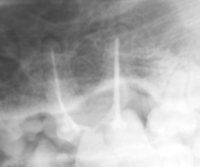

感 染 根 管

目の下に穴があいており膿汁が漏出しております。

左上顎P4の根尖膿瘍が認められます。

感染根管治療を行います。

術後10日:写真ではわかりにくいですが穴は塞がり完治しています。

上記は患者様のご協力により掲載させていただきました。